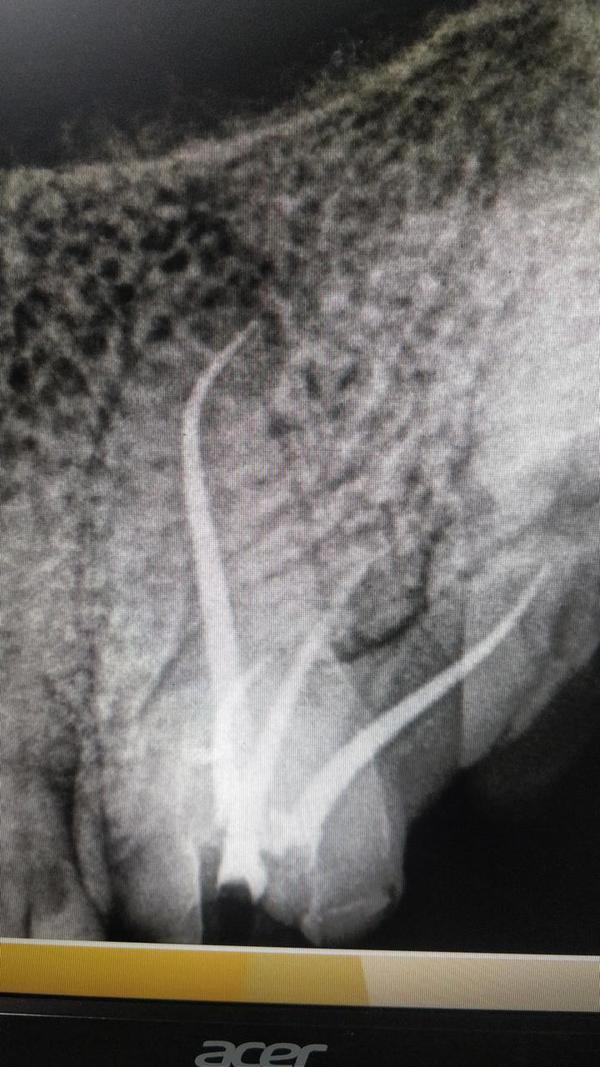

Dental implants are titanium posts surgically placed in the jawbone to replace the root of a missing tooth, providing a stable base for an artificial tooth, crown, bridge, or denture. They function, look, and feel like natural teeth, offer a long-lasting solution, and help prevent jawbone loss. The process involves surgically placing the implant, allowing time for it to fuse with the bone, and then attaching an abutment and artificial tooth